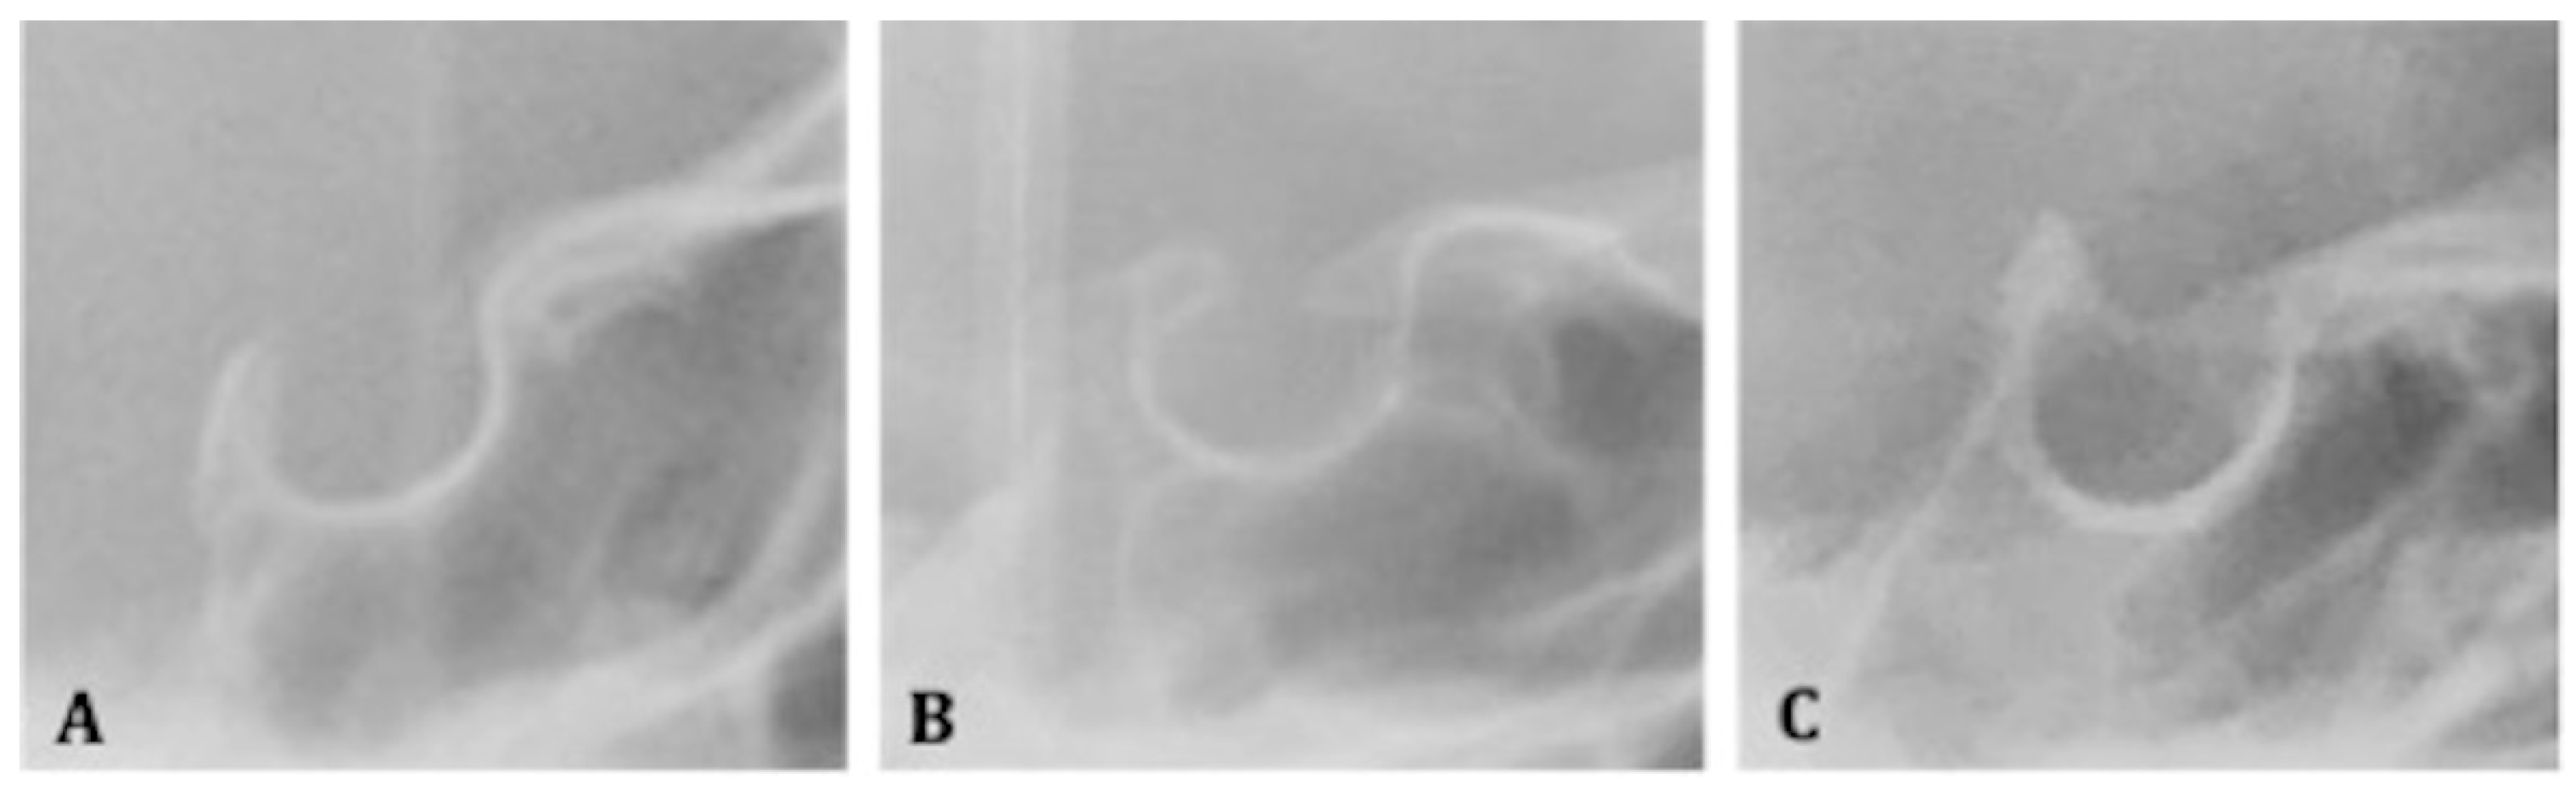

2.5.3. Bridging of the Sella Turcica

- -

- Class I (absence of calcification): when the length is greater than or equal to three- quarters of the greatest anteroposterior diameter;

- Class II (incomplete or partial calcification): when the length is less than or equal to three-quarters of the greatest anteroposterior diameter;

- Class III (complete calcification): when the diaphragm of the sella is evident on the radiograph (Figure 2A–C).